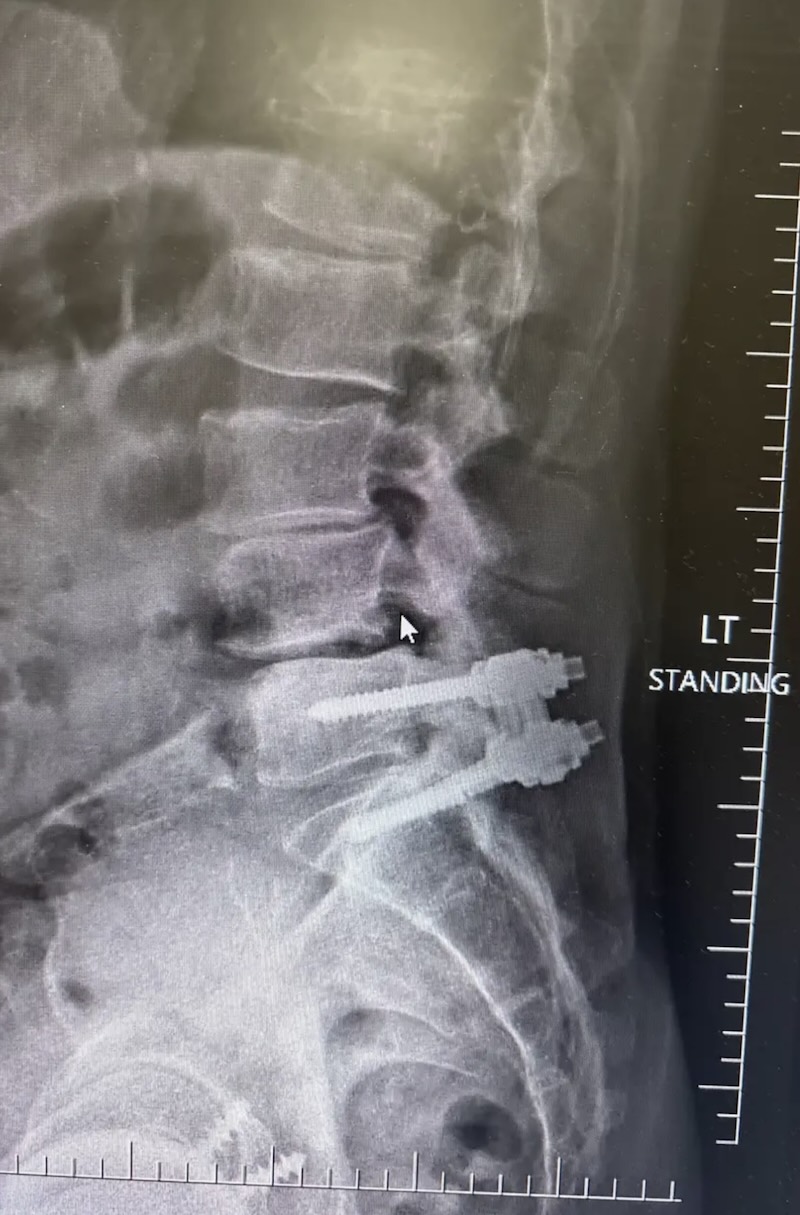

The MONARCH Spine System was originally produced by DePuy and is a titanium thoracolumbar pedicle screw fixation system. It is characterized by the pedicle screw with a polyaxial offset plate.